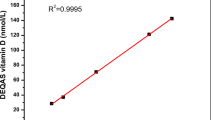

Sample detection

Fasting blood was drawn from 8 a.m. to 10 a.m., and serum biochemical assay was completed on the same day. All 25(OH)D and PTH tests were conducted by the electrochemiluminescence assay on Cobas e601 analyzer (Roche Diagnostics, Switzerland). According to manufacturer’s instructions, the measuring range of 25(OH)D assay was 7.5–175 nmol/L, and the within-assay coefficient of variation (CV) was < 6.8% and the intermediate CV was < 13.1%. A method comparison had been conducted to cross-calibrate the results of immunoassay: 25(OH)D concentrations of 909 samples measured by the Cobas e601 assay (Ccobas) were compared with those by an LC–MS/MS assay(CMS) (Calibra Laboratory, Beijing, China), and the LC–MS/MS assay was aligned with NIST SRM 972a and accepted by CAP(College of American Pathologists). Then all immunoassay 25(OH)D concentrations were converted to LC–MS/MS equivalents following the equation: CMS = 1.039*Ccobas + 0.497, R2 = 0.591 (Supplementary Fig. 1) before analysis. For the second-generation PTH assay, the functional sensitivity was 6.0 pg/mL, and the reference range was 15–65 ng/L. Other biochemical parameters were measured on Cobas c501 analyzer (Roche Diagnostics, Switzerland). Albumin-adjusted serum calcium was calculated by adding the factor 0.02 × (43-albumin concentration in g/L) to the measured serum calcium concentration [19]. EGFR was calculated using the CKD-EPI equation [20]. For all laboratory analyses, the analyzer performance was monitored daily, and a national external quality assessment (EQA) was conducted to ensure the assay quality.